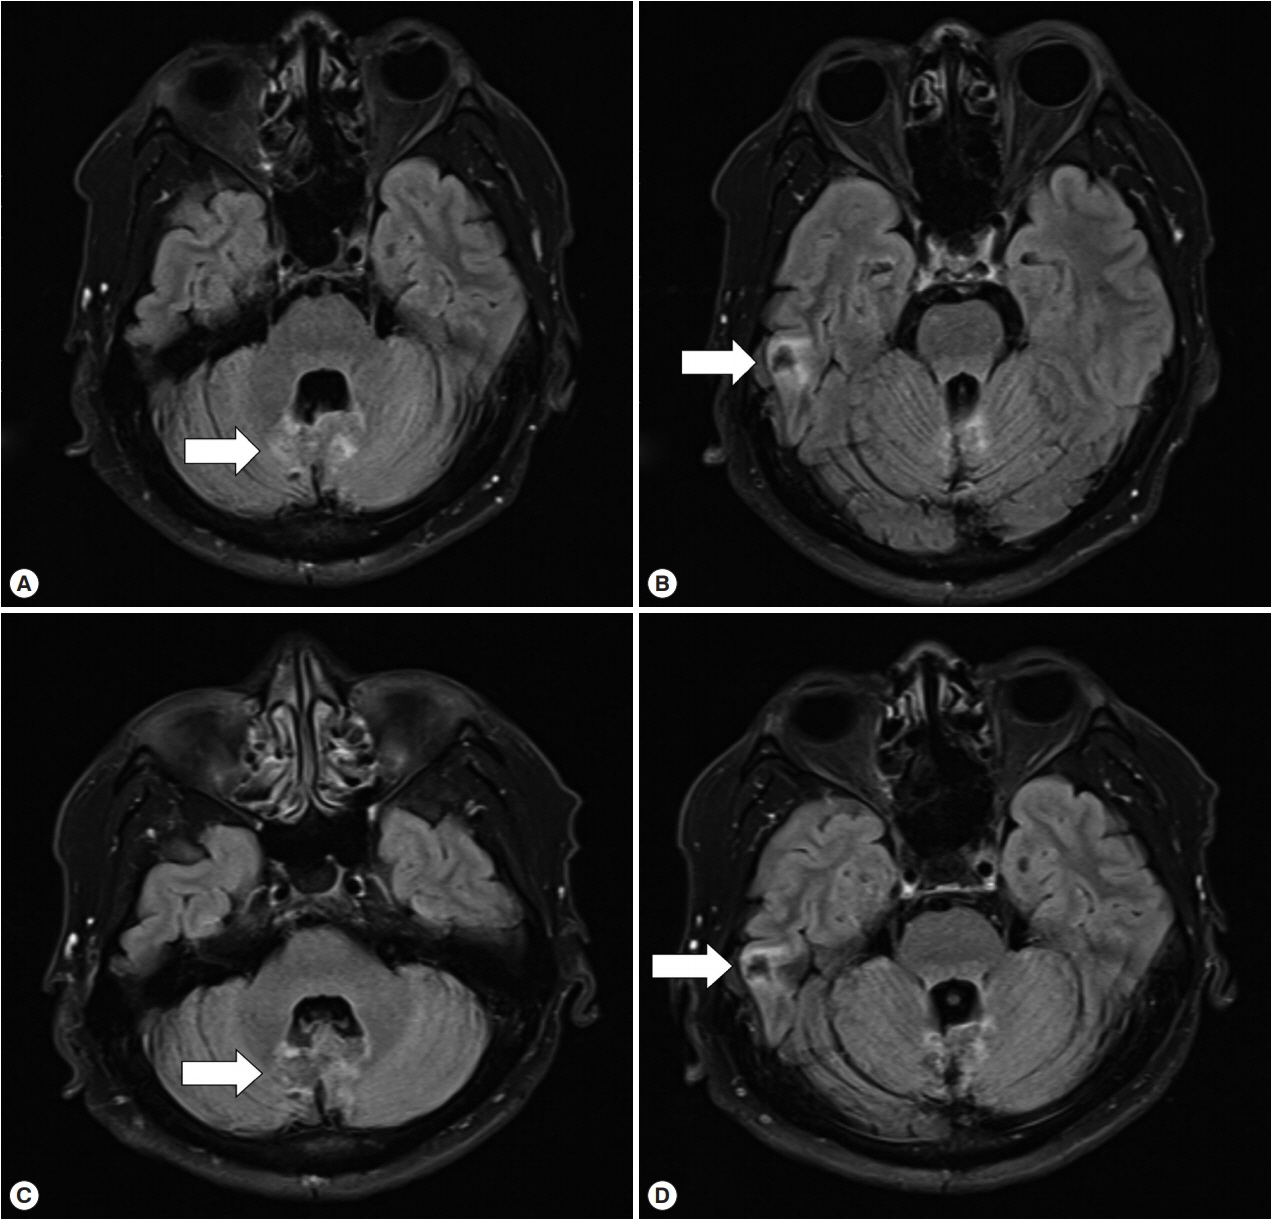

In August 2018, the patient visited our hospital because of worsening symptoms. This was the third university-affiliated hospital he had visited during the course. At admission, his vital signs and laboratory tests were all within normal limits except for mild elevation of eosinophils (white blood cell count 9,190/μl; segment neutrophils 66.2%, lymphocytes 20.9%, eosinophils 5.8%). Although IgG for cysticercosis was positive again (titer 0.704; cut-off 0.232) by ELISA [7], the diagnosis of neurocysticercosis was doubted because the size and shape of cysts in the liver, lung and brain were not consistent with those of cysticercosis using radiological approaches. Given the past travel history to endemic areas of echinococcosis and the multiple organ involvement of cysts with varying sizes, a serum ELISA for echinococcosis IgG was performed as previously described [8], and turned out to be positive (titer 0.886; cut-off 0.270). The patient was finally diagnosed as probable cystic echinococcosis based on the diagnostic criteria [9]. Since it was technically difficult to excise all lesions from both cerebellar hemispheres and the temporal lobe, albendazole, 400 mg twice a day (10–15 mg/kg/day), was started. Worried about paradoxical worsening of neurological symptoms after the commencement of the treatment, we prescribed 4 mg of dexamethasone 4 times a day for 3 days, and then it had been tapered off over 10 days. His dizziness and dysarthria are gradually improving, and the cerebellar lesions are also radiologically improving at 2 (Fig. 4A, B) and 7 months (Fig. 4C, D) after the commencement of the therapy.